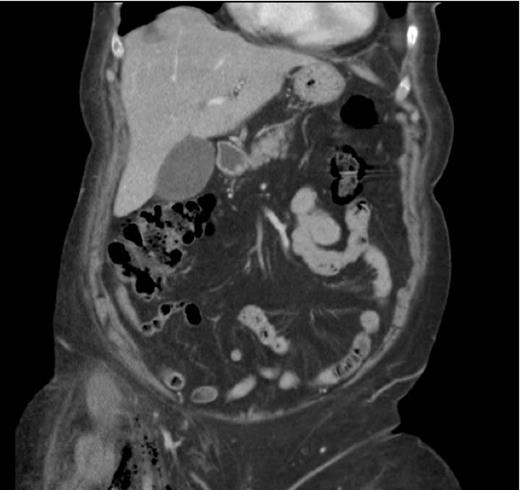

A 75- year old female was admitted as an emergency with right iliac fossa pain. She was afebrile. Bloods on arrival showed leukocytosis of 18.6 and CRP of 235.5. Clinical examination was inconclusive. During her over-night stay, she developed tachycardia and hypotension which responded to fluids. On review, abdominal examination revealed fullness in the right iliac fossa. More importantly she developed swelling and redness of the right thigh. The patient had a CT abdomen, pelvis and upper thigh that showed gas containing fluid collection in the right iliac fossa in keeping with either diverticular or appendicular abscess (Figure 1). It also showed inferior extension of the gas into the right ilio-psoas muscle, groin and upper thigh (perivascular) raising the possibility of necrotising fasciitis (Figure 2).

On laparotomy, an abscess was found in close proximity to a caecal mass. The abscess cavity was entered and a right hemicolectomy was performed. Residual tip of the appendix was found in the abscess cavity. There was no pus tracking retroperitoneally or along the psoas muscle and the muscle looked healthy. A needle aspiration from the swollen upper thigh did not reveal any pus. Most likely cause of the subcutaneous emphysema in thigh was thought to be gas in the abscess cavity tracking along fascial planes. No exploration of the thigh was performed and the plan was to review the thigh swelling the next day. However, this settled down completely following laparotomy alone.